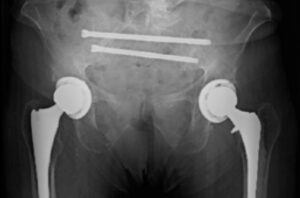

Dr. Brian Cunningham treats a sacral insufficiency fracture with iFuse TORQ TNT® and iFuse TORQ® implants for fracture fixation and SI joint fusion.

Dr. Brian Cunningham uses two iFuse TORQ TNT® implants for sacral fracture fixation and SI joint fusion following low-energy ground-level falls.